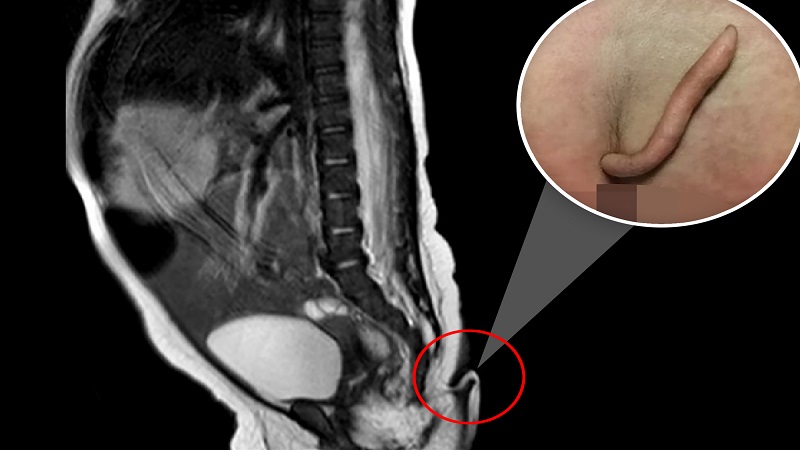

আমাদের কাগজ ডেস্কঃ কন্যাশিশু জন্ম তাও আবার লেজ নিয়ে। শুনতে কিছুটা অবাক মনে হলেও সত্যি। এমন এক বিস্মিত হাসপাতালে কর্মরত চিকিৎসকরাও। সম্প্রতি,এমন ঘটনার সাক্ষী হলও ব্রাজিল। ৬ সেন্টিমিটার লম্বা লেজ নিয়ে জন্ম নিল এক কন্যাশিশু। নিউজিল্যান্ড হেরাল্ডের এক প্রতিবেদনে এই তথ্য পাওয়া গেছে। যা হতবাক করেছেন সবাইকে।

জানা যায়,স্পিনা বিফিডা নামের জটিল রোগ নিয়ে জন্ম নেয় মেয়েটি। তার মেরদণ্ড স্বাভাবিকভাবে বাড়েনি। ফলে শিশুটির মেরুদণ্ড ও শ্রোণিদেশের মাঝে বাড়তি মাংস খণ্ড গজায়। মেরুদণ্ডের সম্প্রসারে যা প্রতিবন্ধকতা সৃষ্টি করে বলে ধারণা করা হচ্ছে।

কর্তব্যরত চিকিৎসকরা জানিয়েছেন, শিশুটির কোমরের মাঝামাঝি এক সরু মাংস খণ্ড গজিয়েছিল। হুবহু তা দেখতে লেজের মতো। ইতোমধ্যে অস্ত্রোপচার করে তা বাদ দেয়া হয়েছে।

চিকিৎসাবিজ্ঞানের ভাষায় একে ‘হিউম্যান সিউডো টেইল’ বলা হয়। সম্প্রতি ‘পেডিয়াট্রিক সার্জারি কেস রিপোর্টস’ নামক জার্নালে শিশুটির বিরল রোগের কথা প্রকাশিত হয়।